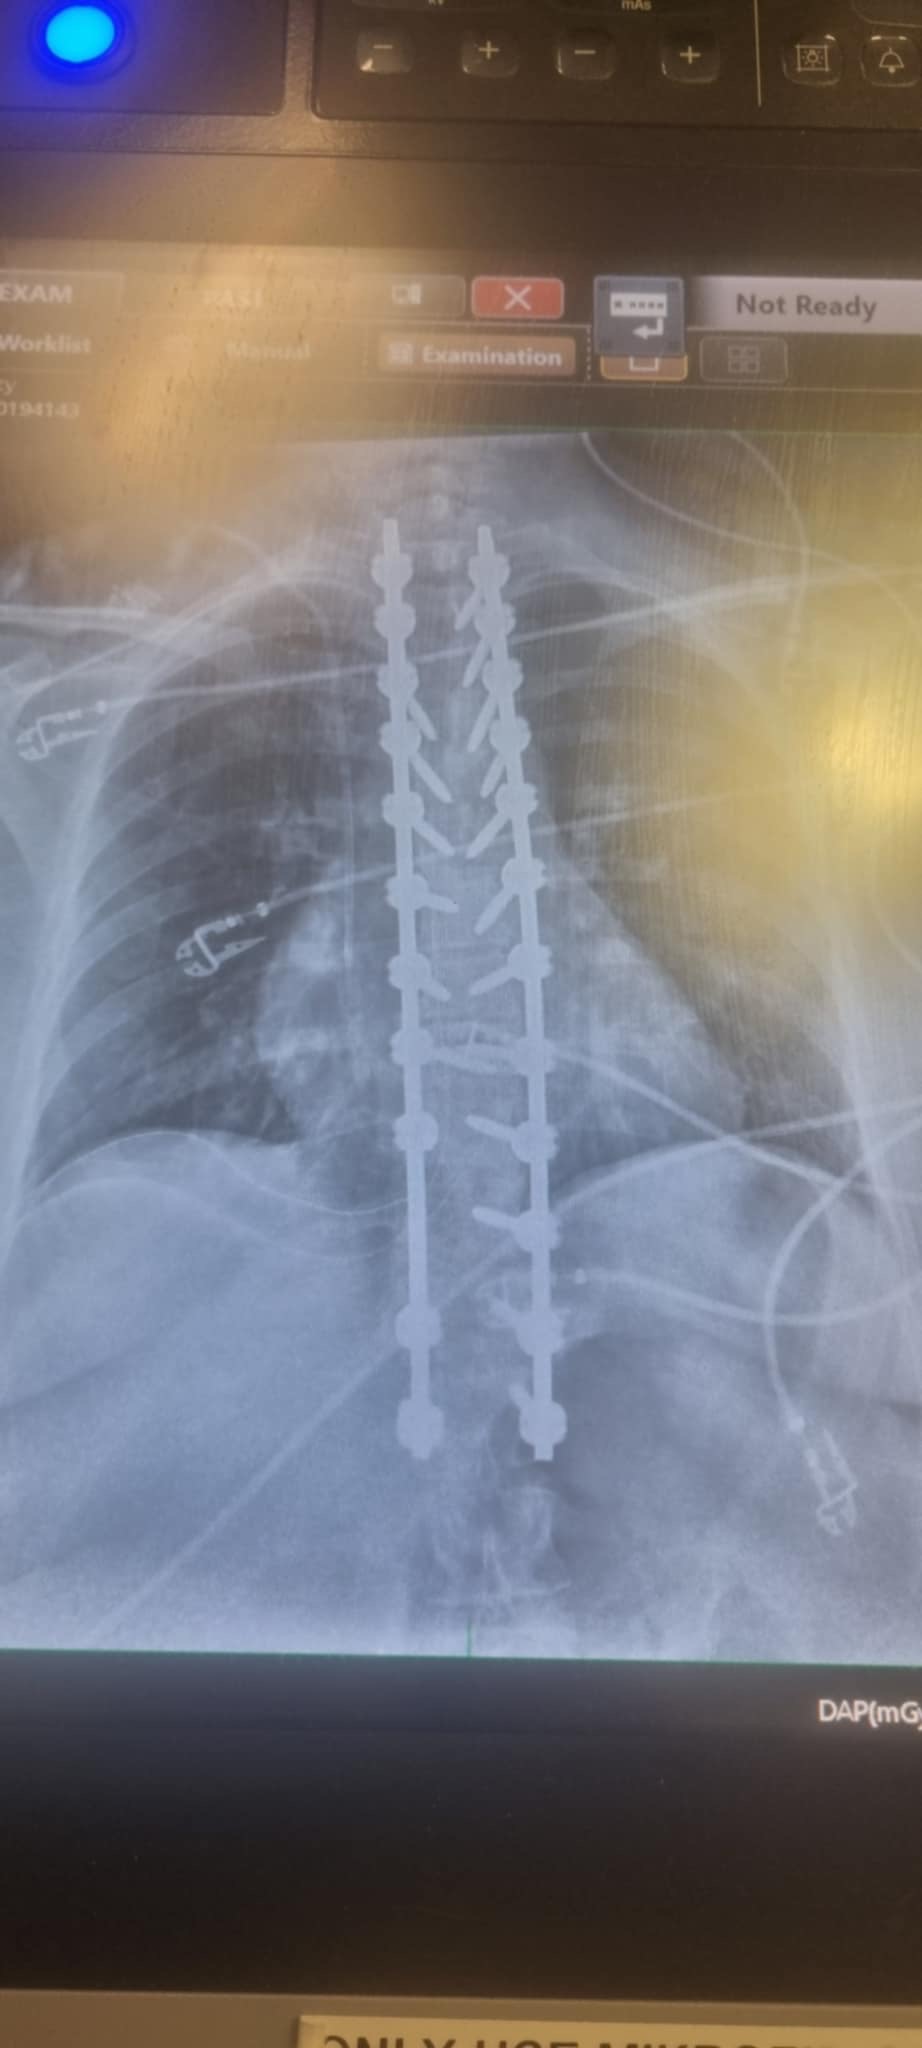

Unfortunately that meant in December last year she needed to be fused from T2-L1. That was on December 10 and then they had to go back in 2 days later to readjust and replace some of the screws. Because the operations were so big, she had lots of blood and plasma transfusions and spent 6 days in the ICU.

2 months later and my mums hump in her middle back has gotten better but her neck and the part of her back between the 2 fusions is now having a lot of pain. Mum can’t turn her head properly or raise her arms up above her shoulders, wash her own hair, shower normally, dress herself, drive, cook, do any cleaning, put on shoes, sit, stand or walk for very long, and if we have to go somewhere further away she needs to be pushed in a wheelchair.